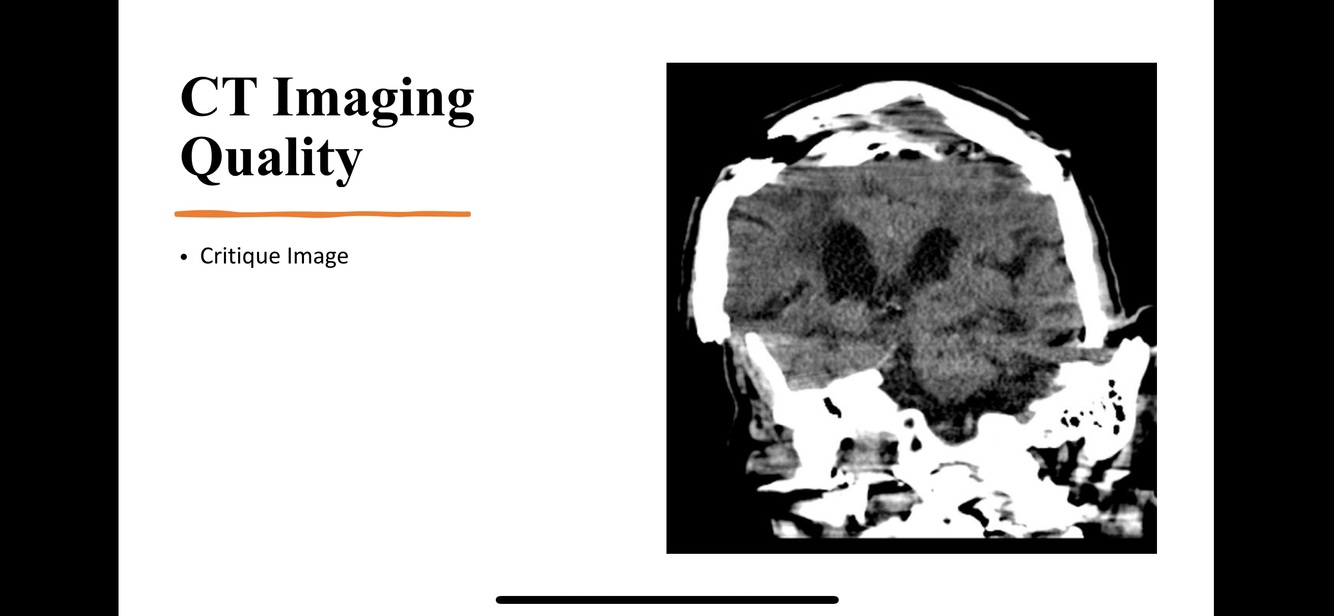

CT Imaging Quality: Critique the image

A

Ring artifacts are a CT phenomenon that occurs due to miscalibration or failure of one or more detector elements in a CT scanner. Less often, it can be caused by insufficient radiation dose or contrast material contamination of the detector cover 2. They occur close to the isocentre of the scan and are usually visible on multiple slices at the same location. They are a common problem in cranial CT. Recalibration of the scanner will usually rectify the artifact. Occasionally detector elements need replacing which can be costly. The referring clinician should be notified that the concerning ring shadows are artifactual.